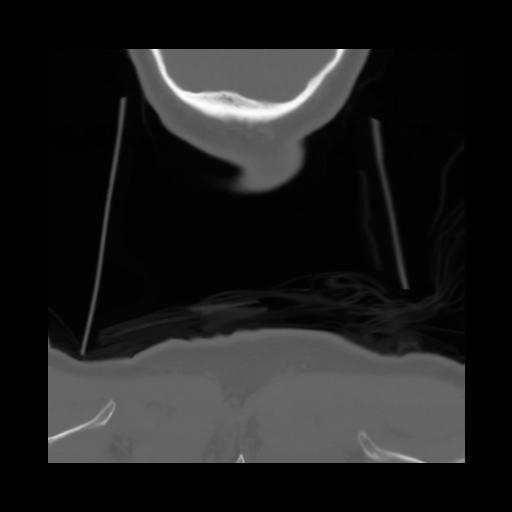

13 P.BLANDAS,,Coronal,2.000,P.BLANDAS,Coronal,